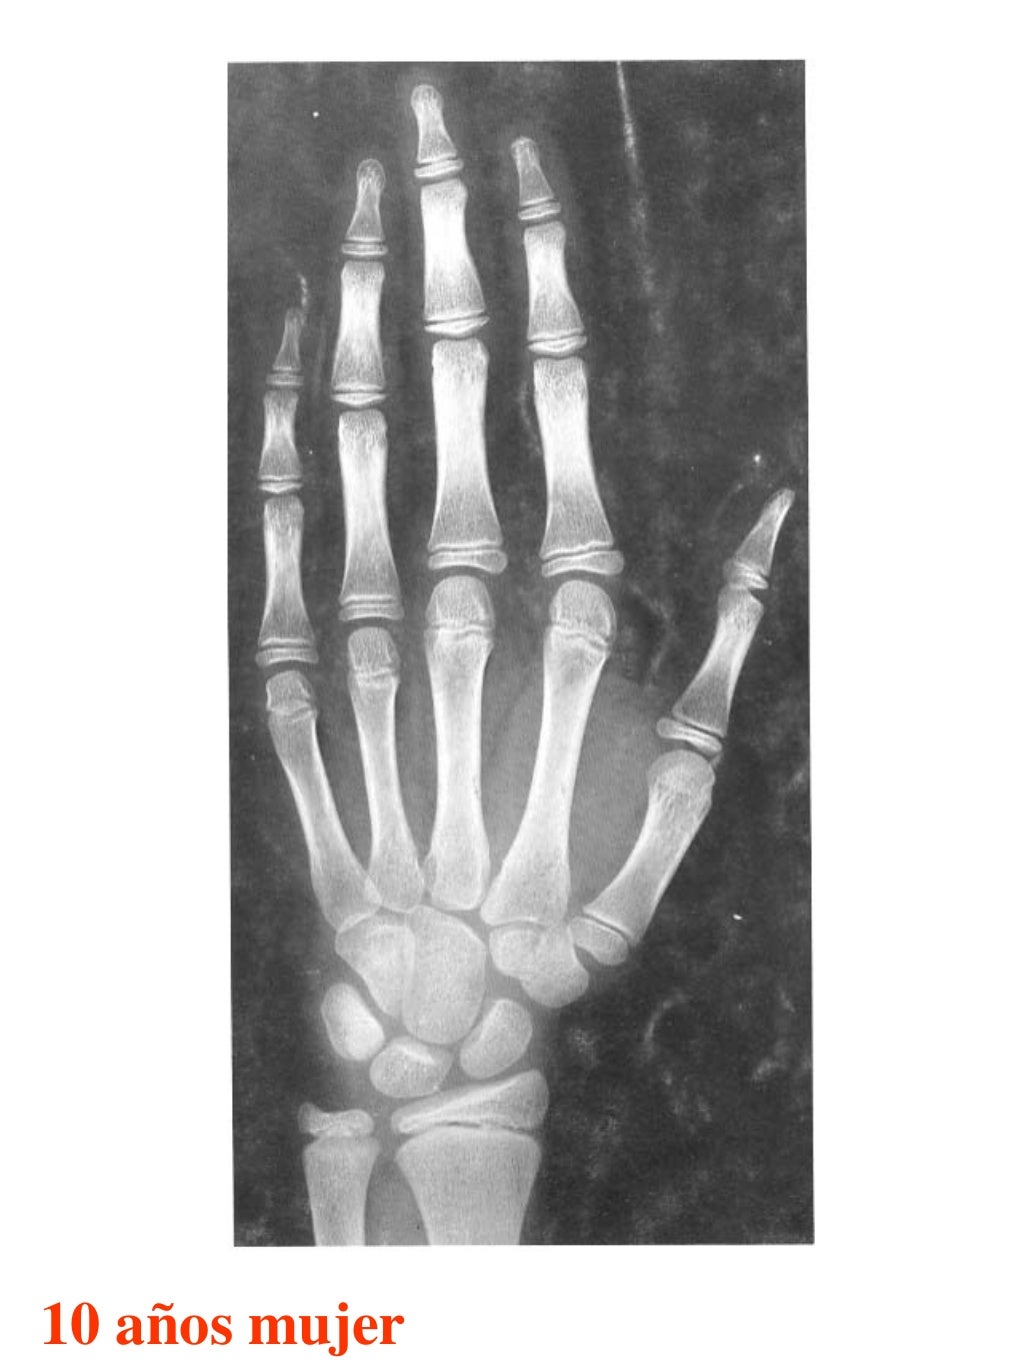

Tablas De Greulich Y Pyle The standards established by greulich and pyle, undoubtedly the most popular method, consist of two series of standard plates. The standards established by greulich and pyle, undoubtedly the most popular method, consist of two series of standard plates. El documento lista las edades. This systematic review summarizes the. The greulich and pyle method is one of the two main ways to assess the bone age of children. Both main methods of bone age. Scribd is the world's largest social reading and publishing site. 153 recomendaciones • 616,869 vistas. Atlas greulich y pyle | pdf | descarga gratuita. The greulich and pyle atlas is used to estimate the age of children and adolescents. The radiographic atlas of skeletal development of the hand and wrist by ww greulich and si pyle is a classic radiological.

Tablas De Greulich Y Pyle . Scribd is the world's largest social reading and publishing site. This systematic review summarizes the. The radiographic atlas of skeletal development of the hand and wrist by ww greulich and si pyle is a classic radiological. The standards established by greulich and pyle, undoubtedly the most popular method, consist of two series of standard plates. The greulich and pyle method is one of the two main ways to assess the bone age of children. El documento lista las edades. Both main methods of bone age. 153 recomendaciones • 616,869 vistas. Atlas greulich y pyle | pdf | descarga gratuita. The greulich and pyle atlas is used to estimate the age of children and adolescents.